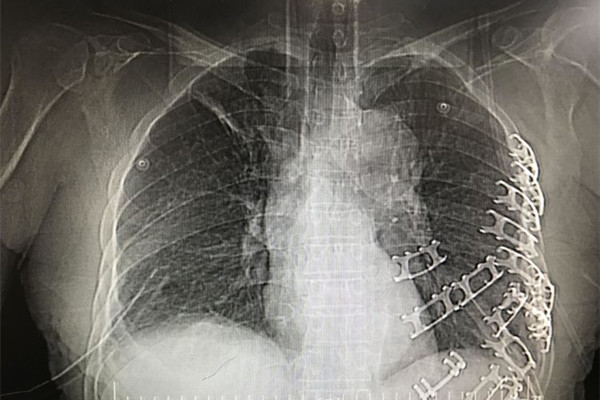

患者李某,在工作时不慎被搅拌机绞压胸腹部及左上肢,急诊转入我院时,颜面部青紫,上半身遍布出血点,左侧胸廓塌陷,反常呼吸明显,右侧呼吸音明显减弱,腹部压痛明显,左上肢严重毁损,情况十分危急。急诊科医护人员立即开通绿色通道,快速完成CT检查,实施紧急救治,并通知胸心外科和麻醉科及辅助科室做好抢救准备。结果提示,患者左侧多根多处肋骨骨折、左侧胸腔积液、右侧膈疝、脾脏破裂,肝脏挫伤,左上肢粉碎性骨折。

患者胸腹部挤压伤并创伤性窒息,病情极其危重,随时都会有生命危险,容不得半点耽搁。在对患者病情与手术方案进行细致的讨论后,由我院胸外科、创伤骨科、普外科、手麻科等科室专家组成的医疗团队立即对患者进行急诊手术抢救。胸外组经胸腔镜辅助行双侧胸腔探查见左侧4-12肋骨骨折,其中4-10肋骨成粉碎性骨折,左肺下叶广泛挫裂伤,胸腔积血2000余毫升,双侧膈肌破裂、肝脏完全疝入右侧胸腔。普外组探查腹腔积血1000余毫升、脾脏破裂。创伤骨科组探查见左上肢粉碎性骨折,软组织毁损严重,在多学科协作下成功完成左侧血胸清除、肺修补、左侧膈肌修补、左侧肋骨骨折复位内固定术等手术。各学科争分夺秒,配合默契,凭借着娴熟的医疗技术和丰富的临床经验,让奄奄一息的患者重获新生。